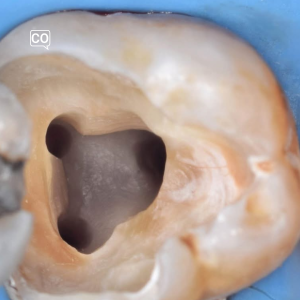

- Responde a las preguntas sobre la imagen.